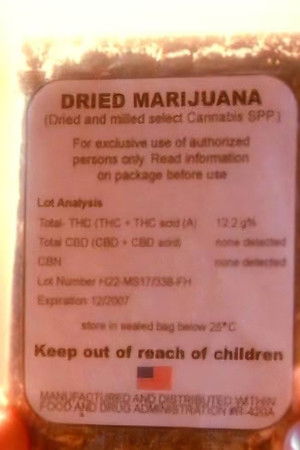

Jane, a struggling but perpetually stoned actress, has a busy day ahead. She has several important tasks on her list, including buying more marijuana. Even though she already has a good start on the day's planned drug use, she eats her roommate's pot-laced cupcakes and embarks on a series of misadventures all over Los Angeles.